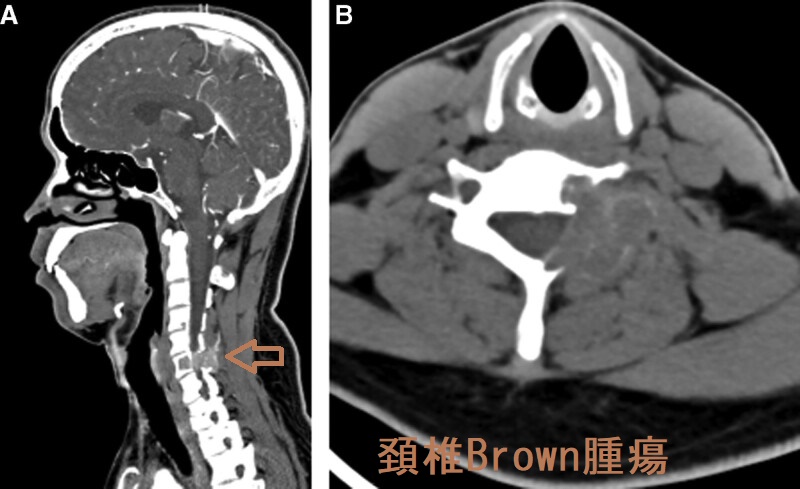

また、長期に渡って進行した反応性線維性骨炎はBrown腫瘍(Brown tumor、ブラウン腫瘍、褐色腫瘍)を形成し、癌の骨転移と鑑別が必要です。Brown腫瘍(ブラウン腫瘍、褐色腫瘍)は組織学的に破骨細胞増生と骨吸収像、ヘモジデリン沈着などが見られ、骨巨細胞腫に類似。

褐色腫瘍(ブラウン腫瘍、Brown腫瘍)は下顎にも発生します。褐色腫瘍(ブラウン腫瘍、Brown腫瘍)の症状は、骨の膨張、骨痛、病的骨折です。